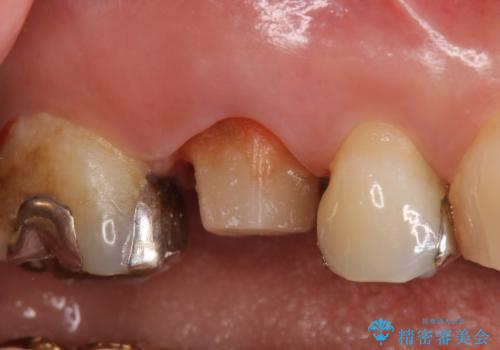

- 右上6番目の銀歯と歯茎の間に隙間ができているのが気になるので診て欲しいといらっしゃった方の症例です。

根管治療も希望されたため、再根管治療終了後、オールセラミッククラウンによる補綴を行いました。